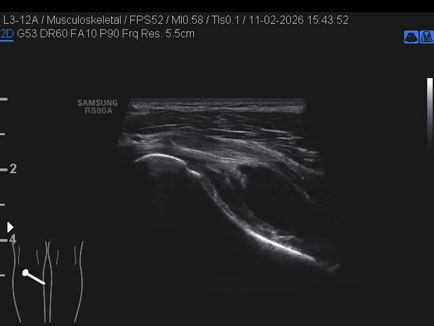

Ecografia del: 11/02/2026

Strumento: Samsung

Sonda: Lineare

Commento all'esame: rottura giunzionale muscolo-tendinea del popliteo.

Conclusioni: rottura miotendinea del muscolo popliteo sinistro (myotendinous tear of the left popliteus muscle).

Realizzazione: Dr. F. Pietro Tarini - Gubbio (PG)